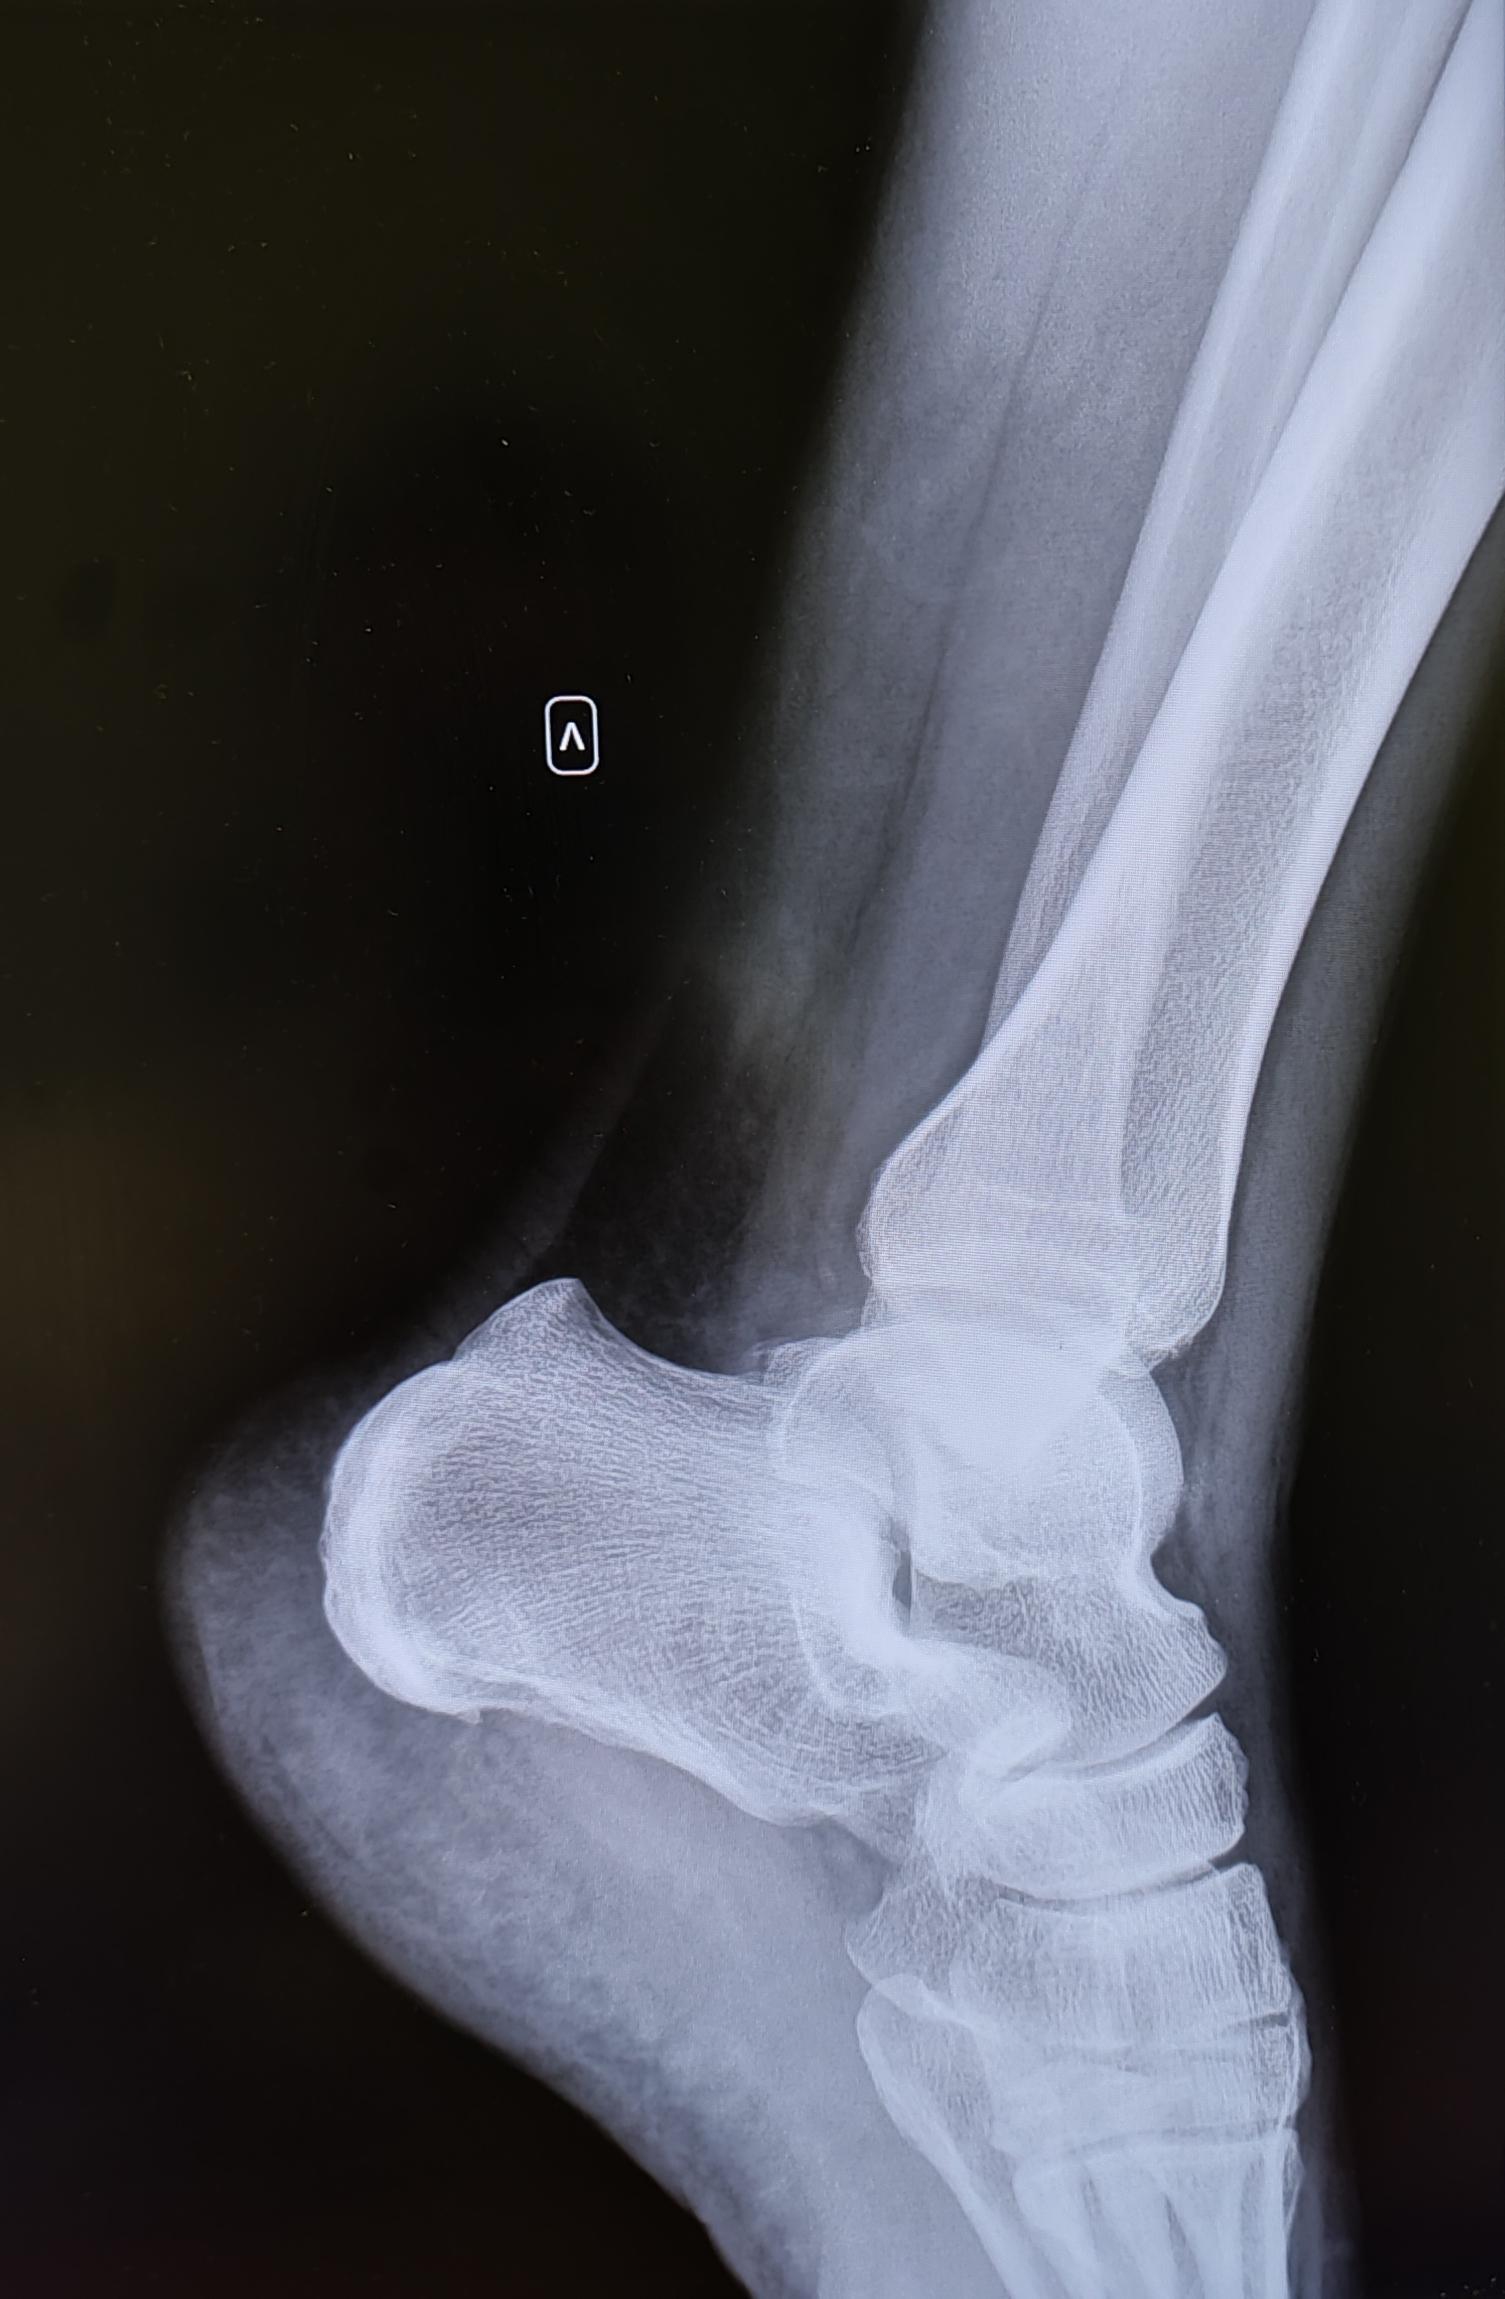

Описание: на Р-граммах правой и левой пяточных костей-травматических, деструктивных изменений не выявлено, структура костной ткани не изменена. В месте прикрепления подошвенных апоневрозов к буграм пяточных костей-визуализируются костные экзостозы. Верхняя часть бугров пяточных костей увеличена в размерах, имеет треугольную форму на широком основании. Заключение: Двусторонняя деформация Хаглунда. Двусторонние пяточные "шпоры".

При отсутствии длительного анамнеза воспалительного процесса, частых обращений с болевым синдромом, стац. лечения по поводу болевого синдрома, решение выносится на основании ст.65(Хирургические болезни и поражения костей, крупных суставов, хрящей:) г, Б-3:призывник годен к военной службе с незначительными ограничениями.